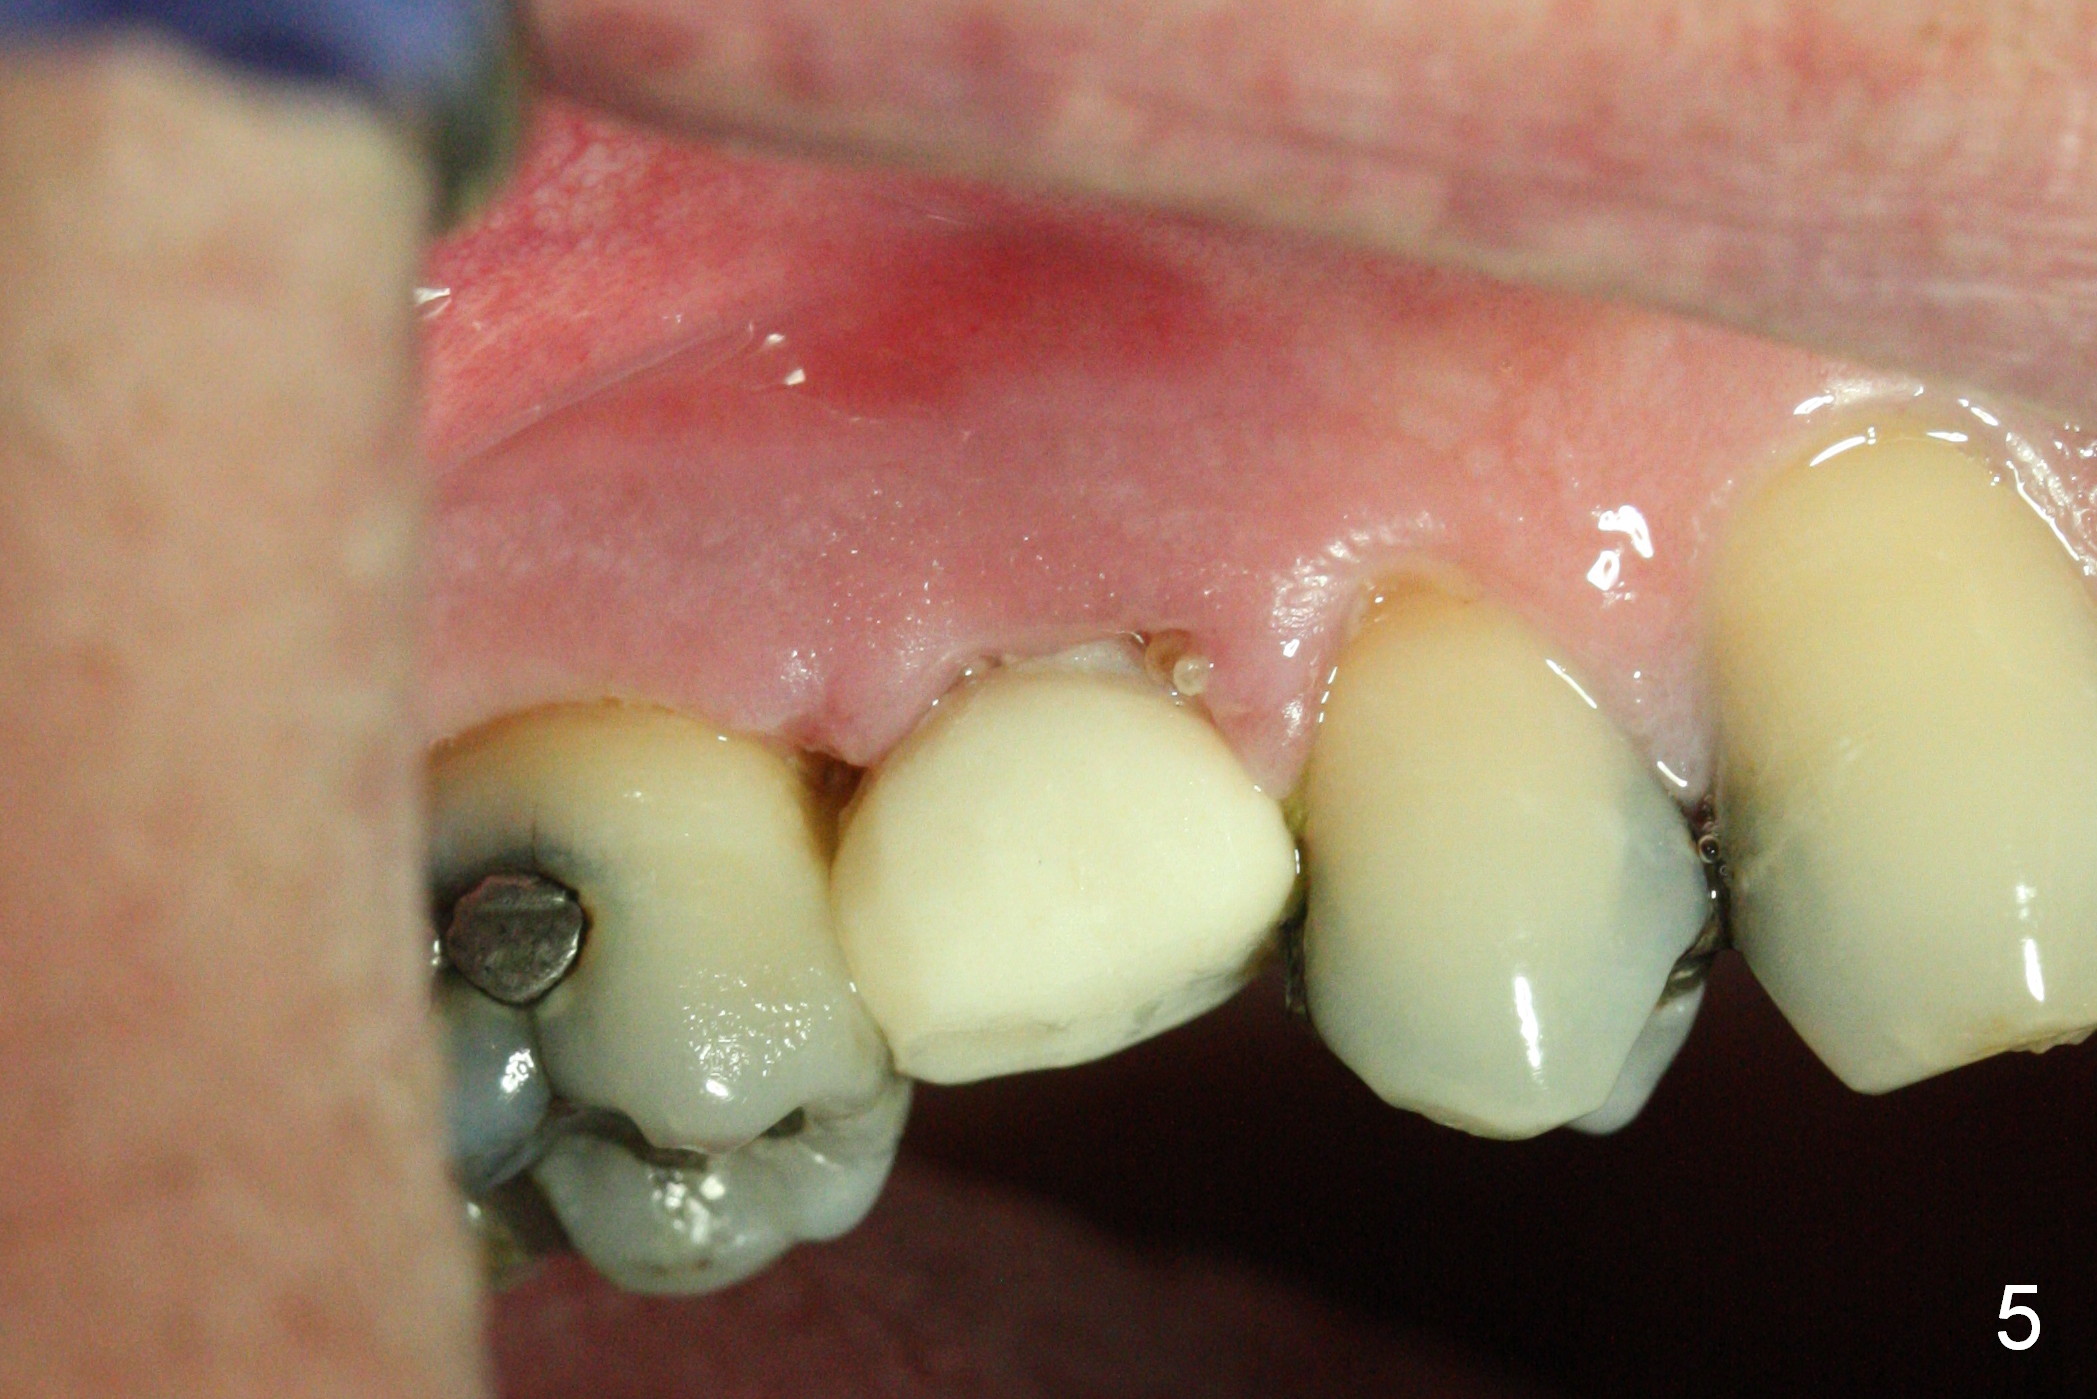

To prevent sinus lift related sinusitis, a shorter implant is going to be placed (Fig.1), approxi-mately 2 mm beyond the apex. Following extraction, the buccal plate (Fig.3a (coronal section): B) is not only ~ 2 mm shorter than the palatal one (P), but also thinner. Since the bone density of the palatal plate is higher, without osteotomy an implant is less likely placed in the middle of the socket (S (Fig.1); Fig.3b) than buccal (Fig.3c). Therefore drills are used to form osteotomy in the apical 1/3 of the palatal slope (Fig.3d (red arrow); SM: sinus membrane). When 3.3 mm Magic Drill (MD) is in place (Fig.2), the distal surface of the sinus septum is perforated without air leakage. Demineralized allograft (.0125-.085) is placed for sinus lift (Fig.4 *) prior to placement of 4.5x11 mm implant with ~ 30 Ncm. The implant is slightly buccal to the ideal position indicated in Fig.3e (curved blue line: sinus lift). A 4.5x4(2) mm pair abutment is placed for an immediate provisional to hold mineralized allograft in the remaining socket gaps (Fig.4 arrowheads, .5-1.5 mm). A 9 mm implant may avoid sinus floor perforation on the distal slope of the 2nd premolar. The osteotomy should have been established initially as mesial as possible. In fact the patient has nasal hemorrhage while sneezing for the first 2 days postop. Although he complains of pain buccal to the implant, the gingiva appears to heal 7 days postop (Fig.5). The distobuccal papilla appears to be displaced somewhat. Raising mucoperiosteal flap is most likely associated with postop pain and esthetic compromise. The implant appears to have osteointegrated 5 months postop (Fig.6). A 4.5 mmx15° 3 mm cuff angled abutment is placed for final restoration. The distolingual portion of the implant is supported by the regenerated bone 3 years post cementation (Fig.7,8).